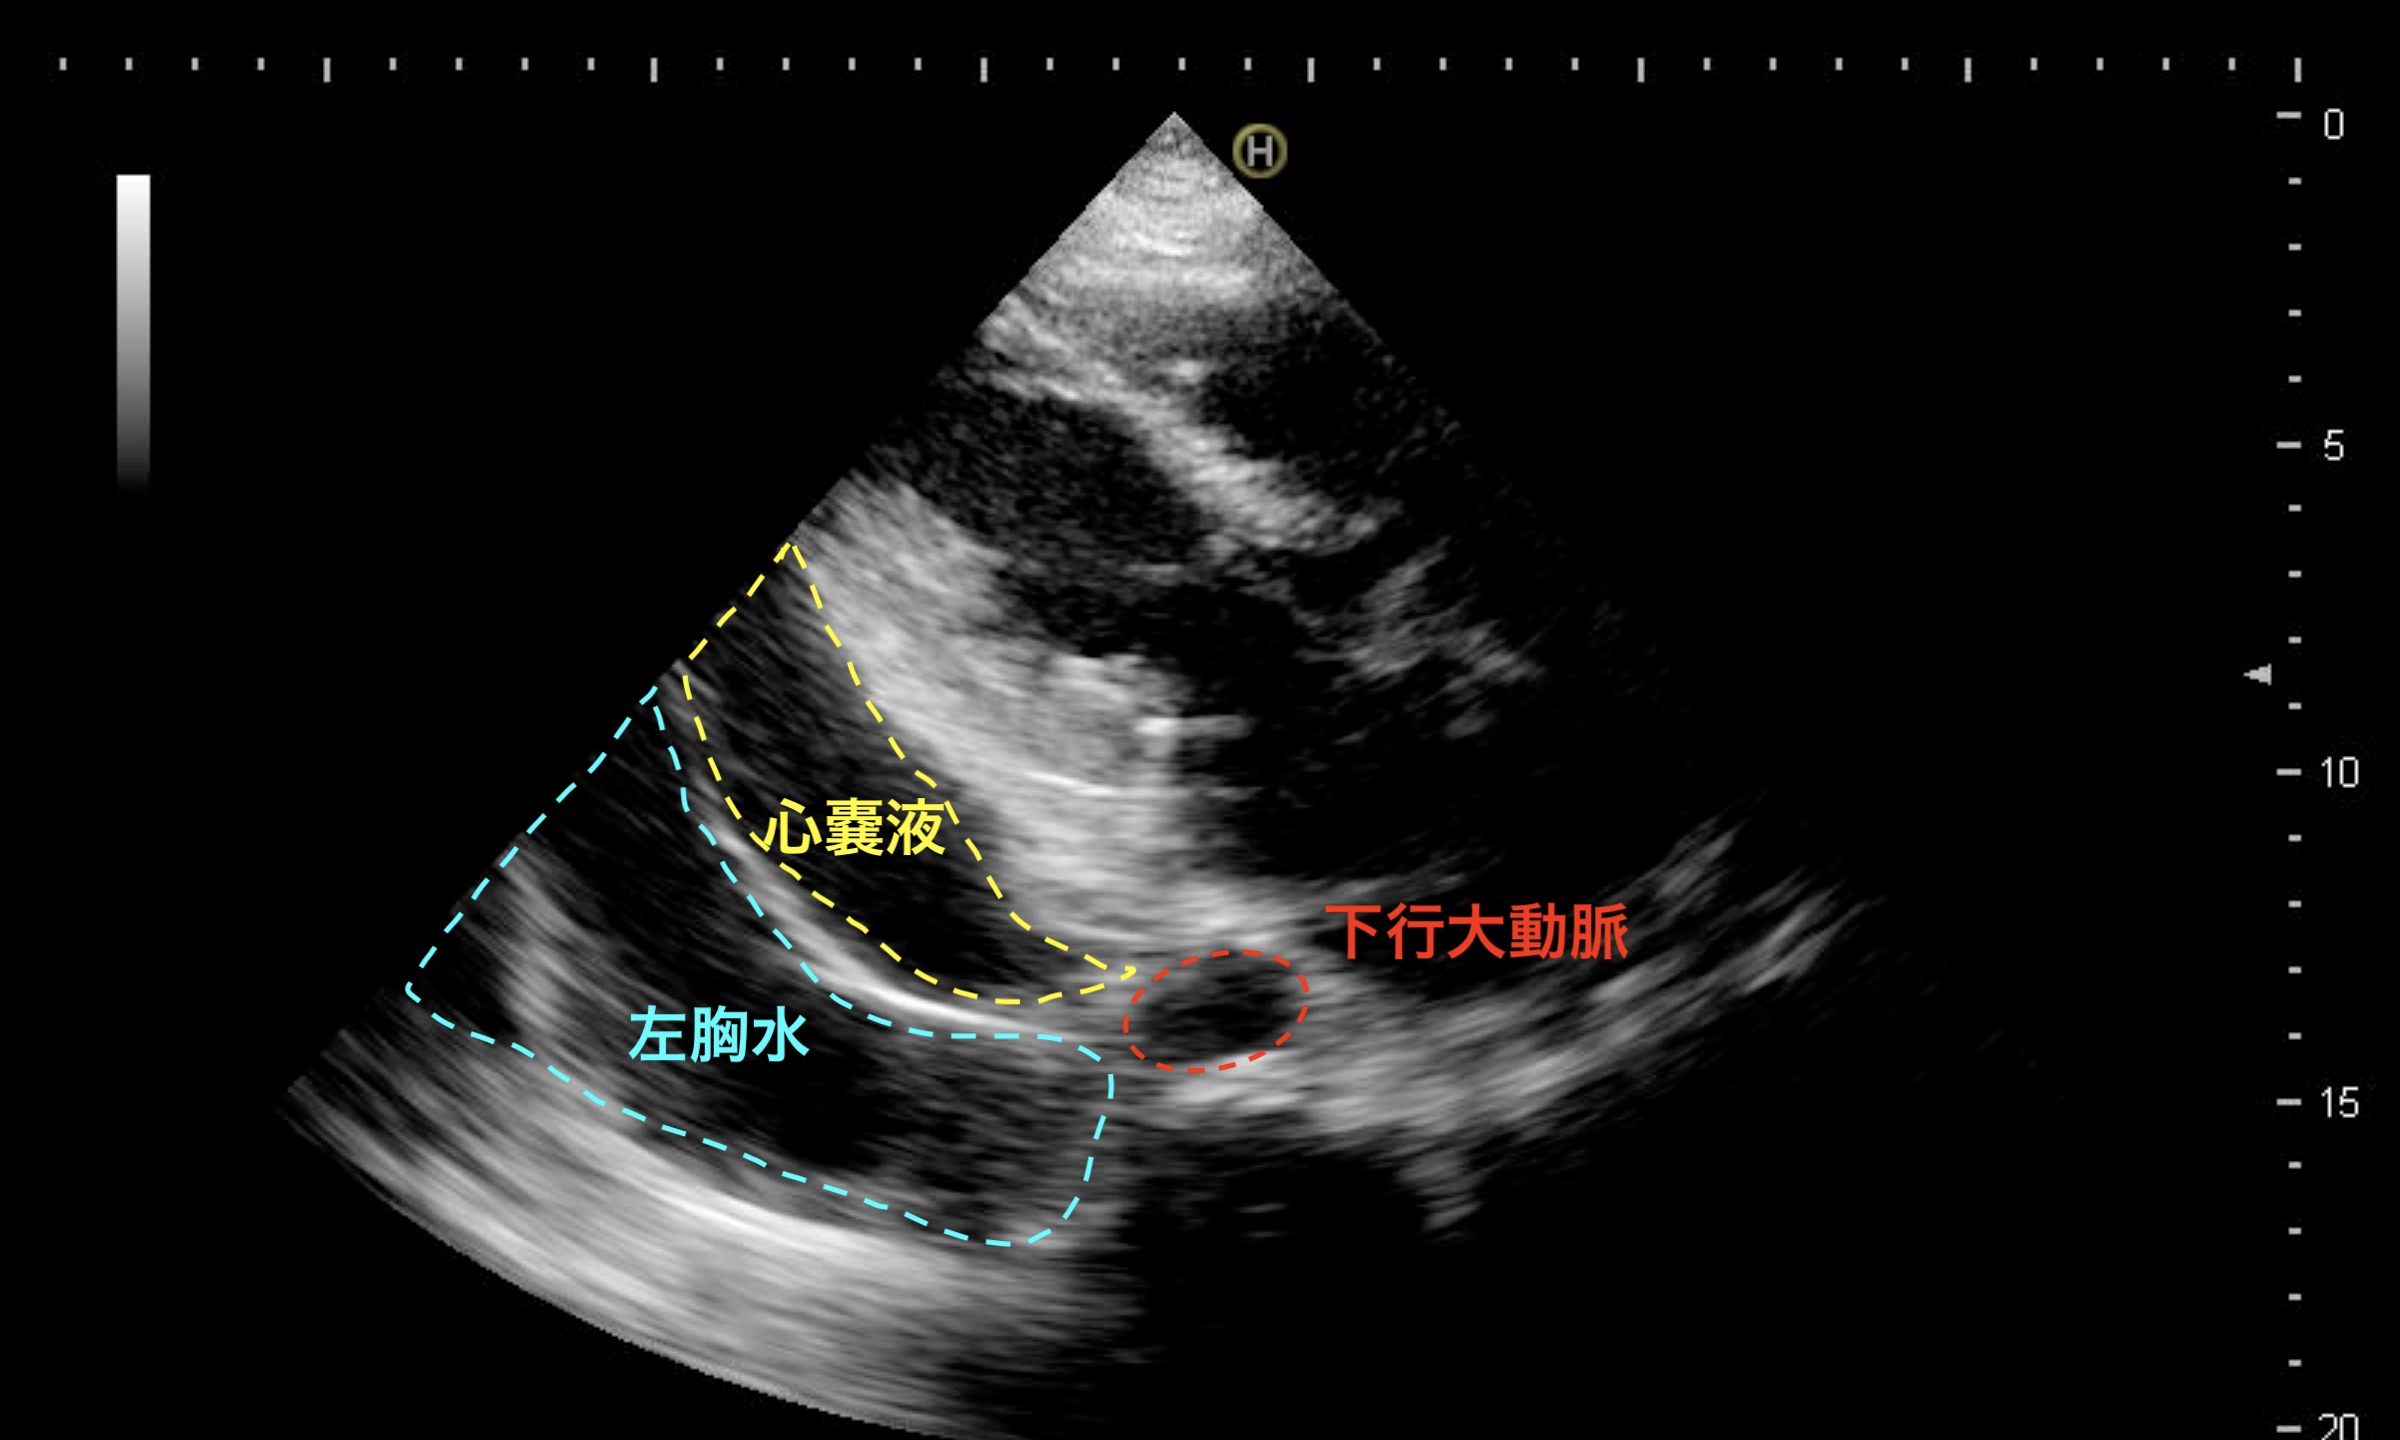

心臓後方にみられる所見はなにか?

心嚢液、左胸水

傍胸骨長軸像で、心臓後方に生じるエコーフリースペースには、心嚢液と左の胸水がある。両者の区別にとって重要なのが、下行大動脈との位置関係である。心嚢水は、下行大動脈と左房との間に収束するように貯留し、左胸水は下行大動脈の後方にまで広がって貯留する。(関連動画:#81)